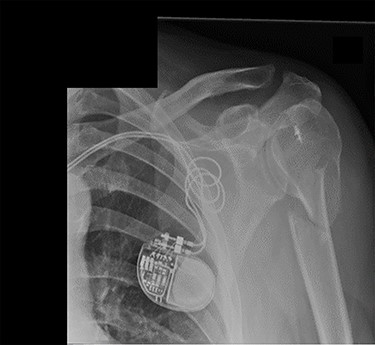

An X-ray of the left shoulder was performed, which revealed acceptable positioning of the fracture. Following a discussion with the patient, a mutual decision was made to manage the injury non-operatively and he was discharged with a collar and cuff sling. Subsequent clinical and radiological review at 1 week and 2 weeks post-injury showed the soft tissues to be healing well and the fracture to be well-positioned (Figs 5 and 6).

Antero-posterior view X-ray taken 1 week post-injury showing acceptable positioning of the fracture.